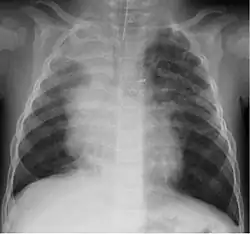

Chest radiograph of a 16-month-old boy in Finland with human bocavirus 1 pneumonia, on day 2 of hospitalization. Bilateral pulmonary infiltrations and atelectasis of the upper right lobe can be seen.

HBoV is found in respiratory samples from healthy subjects.[24] In patients with respiratory complaints, it can be found alone or, more often, in combination with other viruses known to cause respiratory complaints.[6] Newborns are probably protected by passive immunization.[25] The age group most frequently affected appear to be children between the ages of six months to two years,[25][26] although cases in children older than five and even in a 28-year-old have been reported.[27]